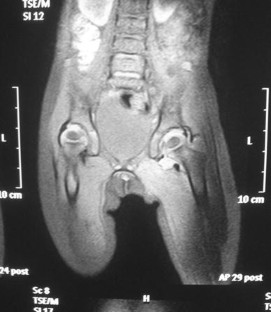

Inflammatory or septic arthritis due to Mp is an extremely unusual manifestation in children, and the functional outcome of the joints is difficult to be predicted. Two cases with Mp infection are presented. The first patient had positive PCR for Mp after hip aspiration and arthrotomy with thorough irrigation and debridement. A flattened femoral head was detected during the follow-up, which became quite spherical a year after. An arthrotomy with medial synovectomy of the knee was performed in the second patient. Lack of full knee extension was presented during the first 3 months, which gradually decreased to 7° in the final follow-up. The suspicion of Mp infection with extra-pulmonary involvement in children is mainly based on clinical, epidemiological and radiological data, but laboratory testing is required for confirmation. Rapid diagnosis of probability consists of serum tests, and their results are essential for early therapeutic planning. The direct diagnosis of Mp DNA through polymerase chain reaction (PCR) provides specificity and sensitivity. Very few cases of arthritis associated with Mp infection have been published but not with the severity of our cases. Clinical suspicion of Mp infection is of great importance, and the outcome depends on early diagnosis and specific treatment.

Fig. 1